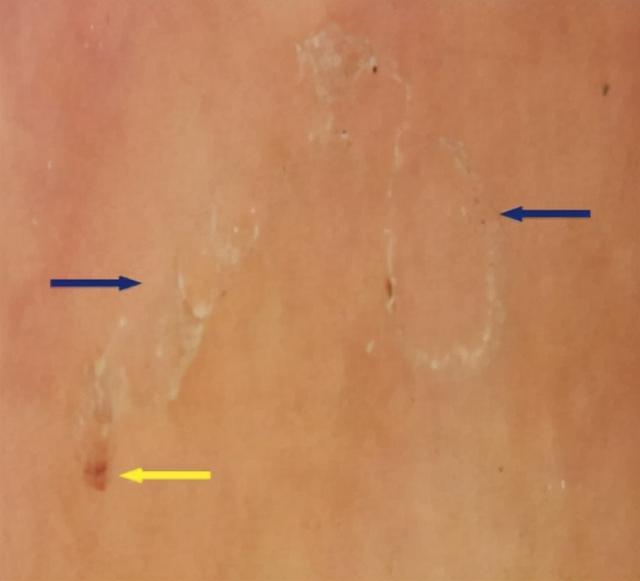

以及灰色的弯曲隆起纹路

长时间不愈会出现血痂、色素沉积等